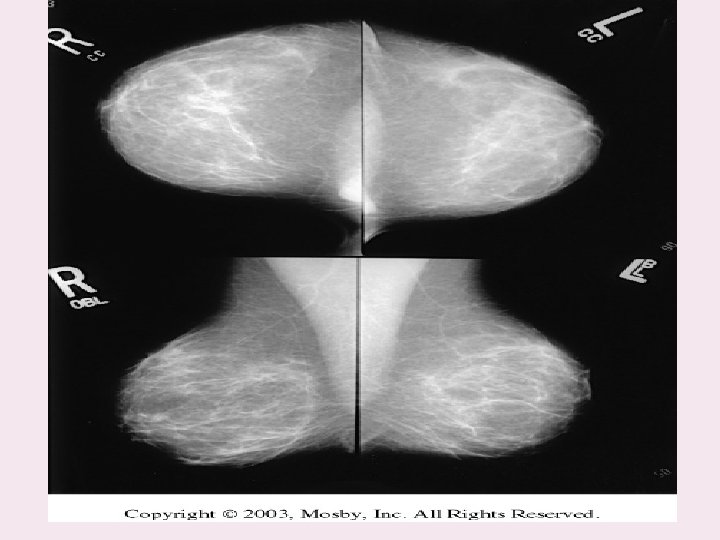

Routine mammography projections Craniocaudal (CC) Mediolateral oblique (MLO)

Recommended projections: - Basic: • 45 -degree medio-lateral oblique projections (Lundgren) ML • Craniocaudal CC

Projections